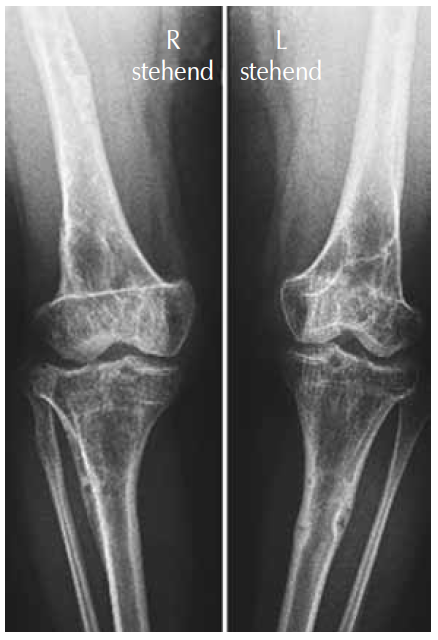

AP knees and lower femora radiographs showed a combination of osteoporosis, osteolytic islands along the cortices, and fibrocartilaginous changes (Fig. 3).

Fig. 3. AP knees and lower femora radiographs showed a combination of osteoporosis, osteolytic islands along the cortices, and fibrocartilaginous changes